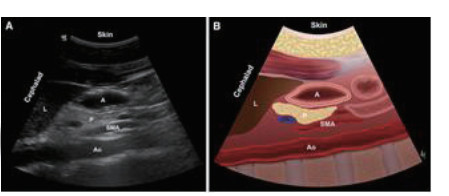

1.2.1 ①胃窦超声评估利用床旁超声机Sonosite M-Tube进行检测,利用2~5 MHz凸阵探头,患者取仰卧位或右侧卧位(因病情危重无法右侧卧位者取仰卧位),床头抬高30~45°,探头方向与身体纵轴平行,在剑突下于正中矢状线右侧获取清晰胃窦部超声[1],见图 1。

| 图 1A 胃窦超声检查部位 |

| 图 1B 胃窦超声切面及示意 |

② 利用超声数据包对胃窦部面积进行描计计算,应用公式[2]:GV(ml)=27.0+14.6×right-lateral CSA-1.28×age,进行评估胃内容物容积,见图 2。